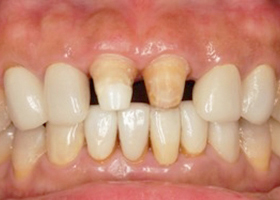

6. 將假牙拆除後,重新取模。

proimages/case/cosmetic/pic_case-028.jpg

proimages/case/cosmetic/pic_case-029.jpg